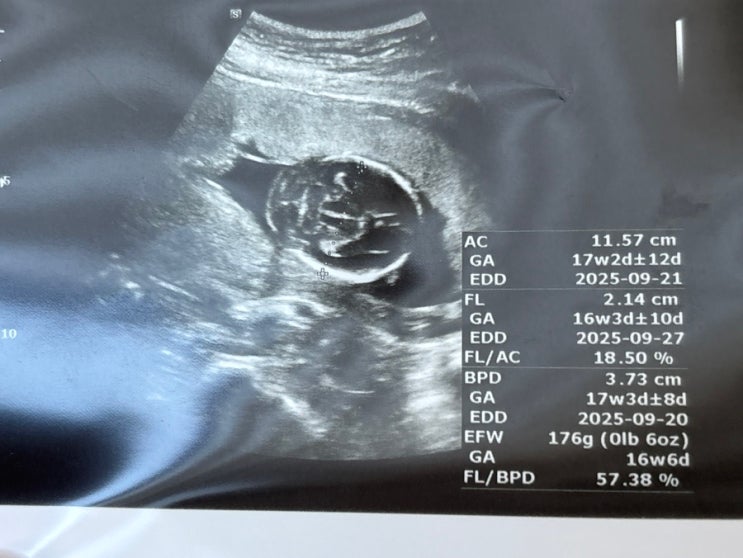

[임신일기 7] 1,2차 기형아 검사 결과 / 17주 서브 병원 성별 확인

성별이 궁금해서 다시 찾은 병원! 여수에 있는 병원 중 좀 크면서(산부인과 쌤 여럿) 가본 적 있는 곳으로 ...